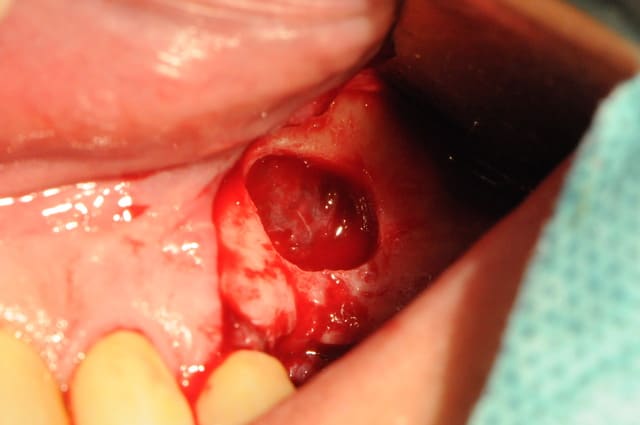

Le deuxième dépucelage concerne mon premier SINUS LIFT.

Mais bon Dieu, tu n'as donc jamais vu une greffe de près ? La fenêtre d'accès au sinus se reconstitue intégralement, le bio oss sera intégré à de l'os nouveau et progressivement résorbé, la valeur biomécanique de l'ensemble sera plus grande au final que celle de l'os de départ ! Et il sera réimplanté une racine artificielle en lieu et place d'une dent qui fait défaut et d'un os qui s'est fait la malle... Tu appelles ça une mutilation ?

- volet osseux : de par ta préparation à la fraise boule il t'était impossible de repositionner le volet osseux en fin de chirugie. La logique voudrait que tu repousses ce volet dans le sinus afin de créer un "pseudo plafond sinusien". A la vue de tes photos il semblerait que tu es tout de même enlevé ce volet. Est ce que je me trompe ? si oui oublies ma question, si non pourquoi ?